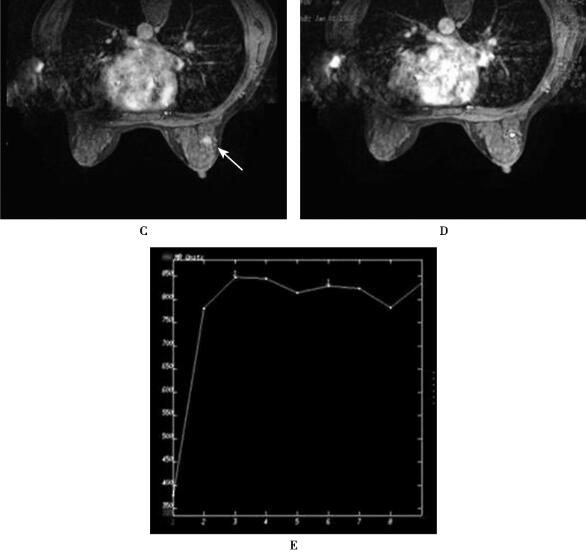

图1(右乳)导管内乳头状瘤

A.T2*WI首次通过灌注图像病灶未见明显灌注;B.灌注时间信号强度曲线呈趋于平台型曲线,未见明显信号丢失;C、D.T1WI动态增强图像,病灶显著均匀强化,边缘较清晰;E.T1WI动态增强时间信号强度曲线表现为平台型(Ⅱ型)

乳腺导管内乳头状瘤因内部成分不同,在T1WI呈等信号、低信号或高信号,T2WI呈高信号或混杂信号,增强MRI表现为早期均匀或不均匀增强结节,动态增强曲线呈平台型或流出型,可伴导管扩张。

该病例鉴别诊断要考虑到乳腺纤维腺瘤,纤维腺瘤的边缘清晰光滑,TIC曲线多呈持续型或平台型,该病例TIC曲线呈平台型,需要与之鉴别诊断。由于该病例的鉴别诊断困难,参考T2*WI首次通过灌注图像,结果病灶无明显灌注,时间-信号强度曲线趋近于平台型,未见信号丢失,这些改变符合良性病变特点,有利于鉴别诊断。